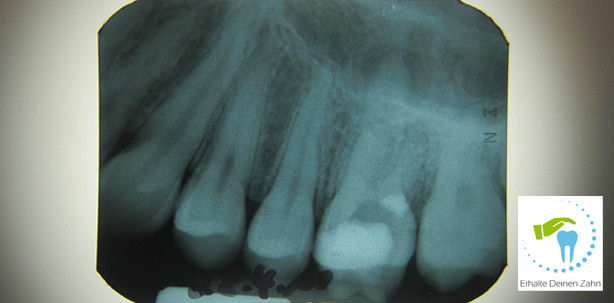

Wurzelkanalbehandlungen sind schwierige zahnärztliche Behandlungen, bei denen Perforationen (unbeabsichtigte Verletzung der Zahnwurzel während der Behandlung) der Wurzelkanalwand, der Zahnkrone oder des Pulpakammerbodens auftreten können. Eine Perforation bildet eine Verbindung zur Mundhöhle, durch die Bakterien und Speichel in den Zahn eindringen können. Liegt die Perforation tiefer in der Wurzel, tritt eine Verbindung zum Kieferknochen auf und die Desinfektion des Wurzelkanals wird schwierig.

Die Wurzelkanalbehandlung ist für viele Zähne die letzte Möglichkeit, diese zu erhalten. Bei einer lange bestehenden Karies bildet der Zahn zum Schutz vermehrt Dentin (Zahnhartsubstanz). Wird aufgrund einer Pulpitis (Entzündung des Zahnnervens) oder einer Pulpanekrose (Absterben des Zahnnervens) eine Wurzelkanalbehandlung notwendig, kann es durch die vermehrte Bildung von Dentin schwierig sein, den Wurzelkanal aufzufinden. Dabei besteht immer die Gefahr, den Wurzelkanal zu perforieren. Durch genaues Befunden des Röntgenbildes vor Beginn der Wurzelkanalbehandlung und Verwendung von Vergrößerungshilfen wie Operationsmikroskop oder Lupenbrille, kann eine Perforation oft vermieden werden. Eine andere Ursache für Perforation eines Zahnes kann die Präparation des Wurzelkanals, vor allem gekrümmter Wurzelkanäle, mit Metallfeilen sein. Wird der Wurzelkanal zu groß präpariert oder kann die Krümmung nicht eingehalten werden, treten sogenannte Strip Perforationen oder eine Via falsa auf.

Eine Perforation kann an der Zahnkrone oberhalb des Knochens sowie im oberen, mittleren und unteren Wurzelkanaldrittel auftreten. Ebenfalls ist es möglich, den Bereich zwischen den Wurzeln zu perforieren. Je nach Lokalisation, Größe und Alter der Perforation ist die Therapie und auch die Prognose für den Zahn unterschiedlich. Liegt eine Perforation an der Zahnkrone, kann diese oft durch eine Kunststofffüllung verschlossen werden. Liegt die Perforation in der Wurzel, gibt es die Möglichkeit, diese mithilfe eines Zementes, MTA, zu verschließen. Dies funktioniert in vielen Fällen sehr gut, allerdings bedarf die Handhabung ausreichend Erfahrung.